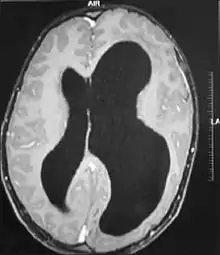

![]() | |

| MRI images showing megalencephaly in four family members who all have unusually large skulls (the family is affected by an autosomal recessive syndrome caused by a KIF7 mutation that induces multiple epiphyseal dysplasia)[1] | |